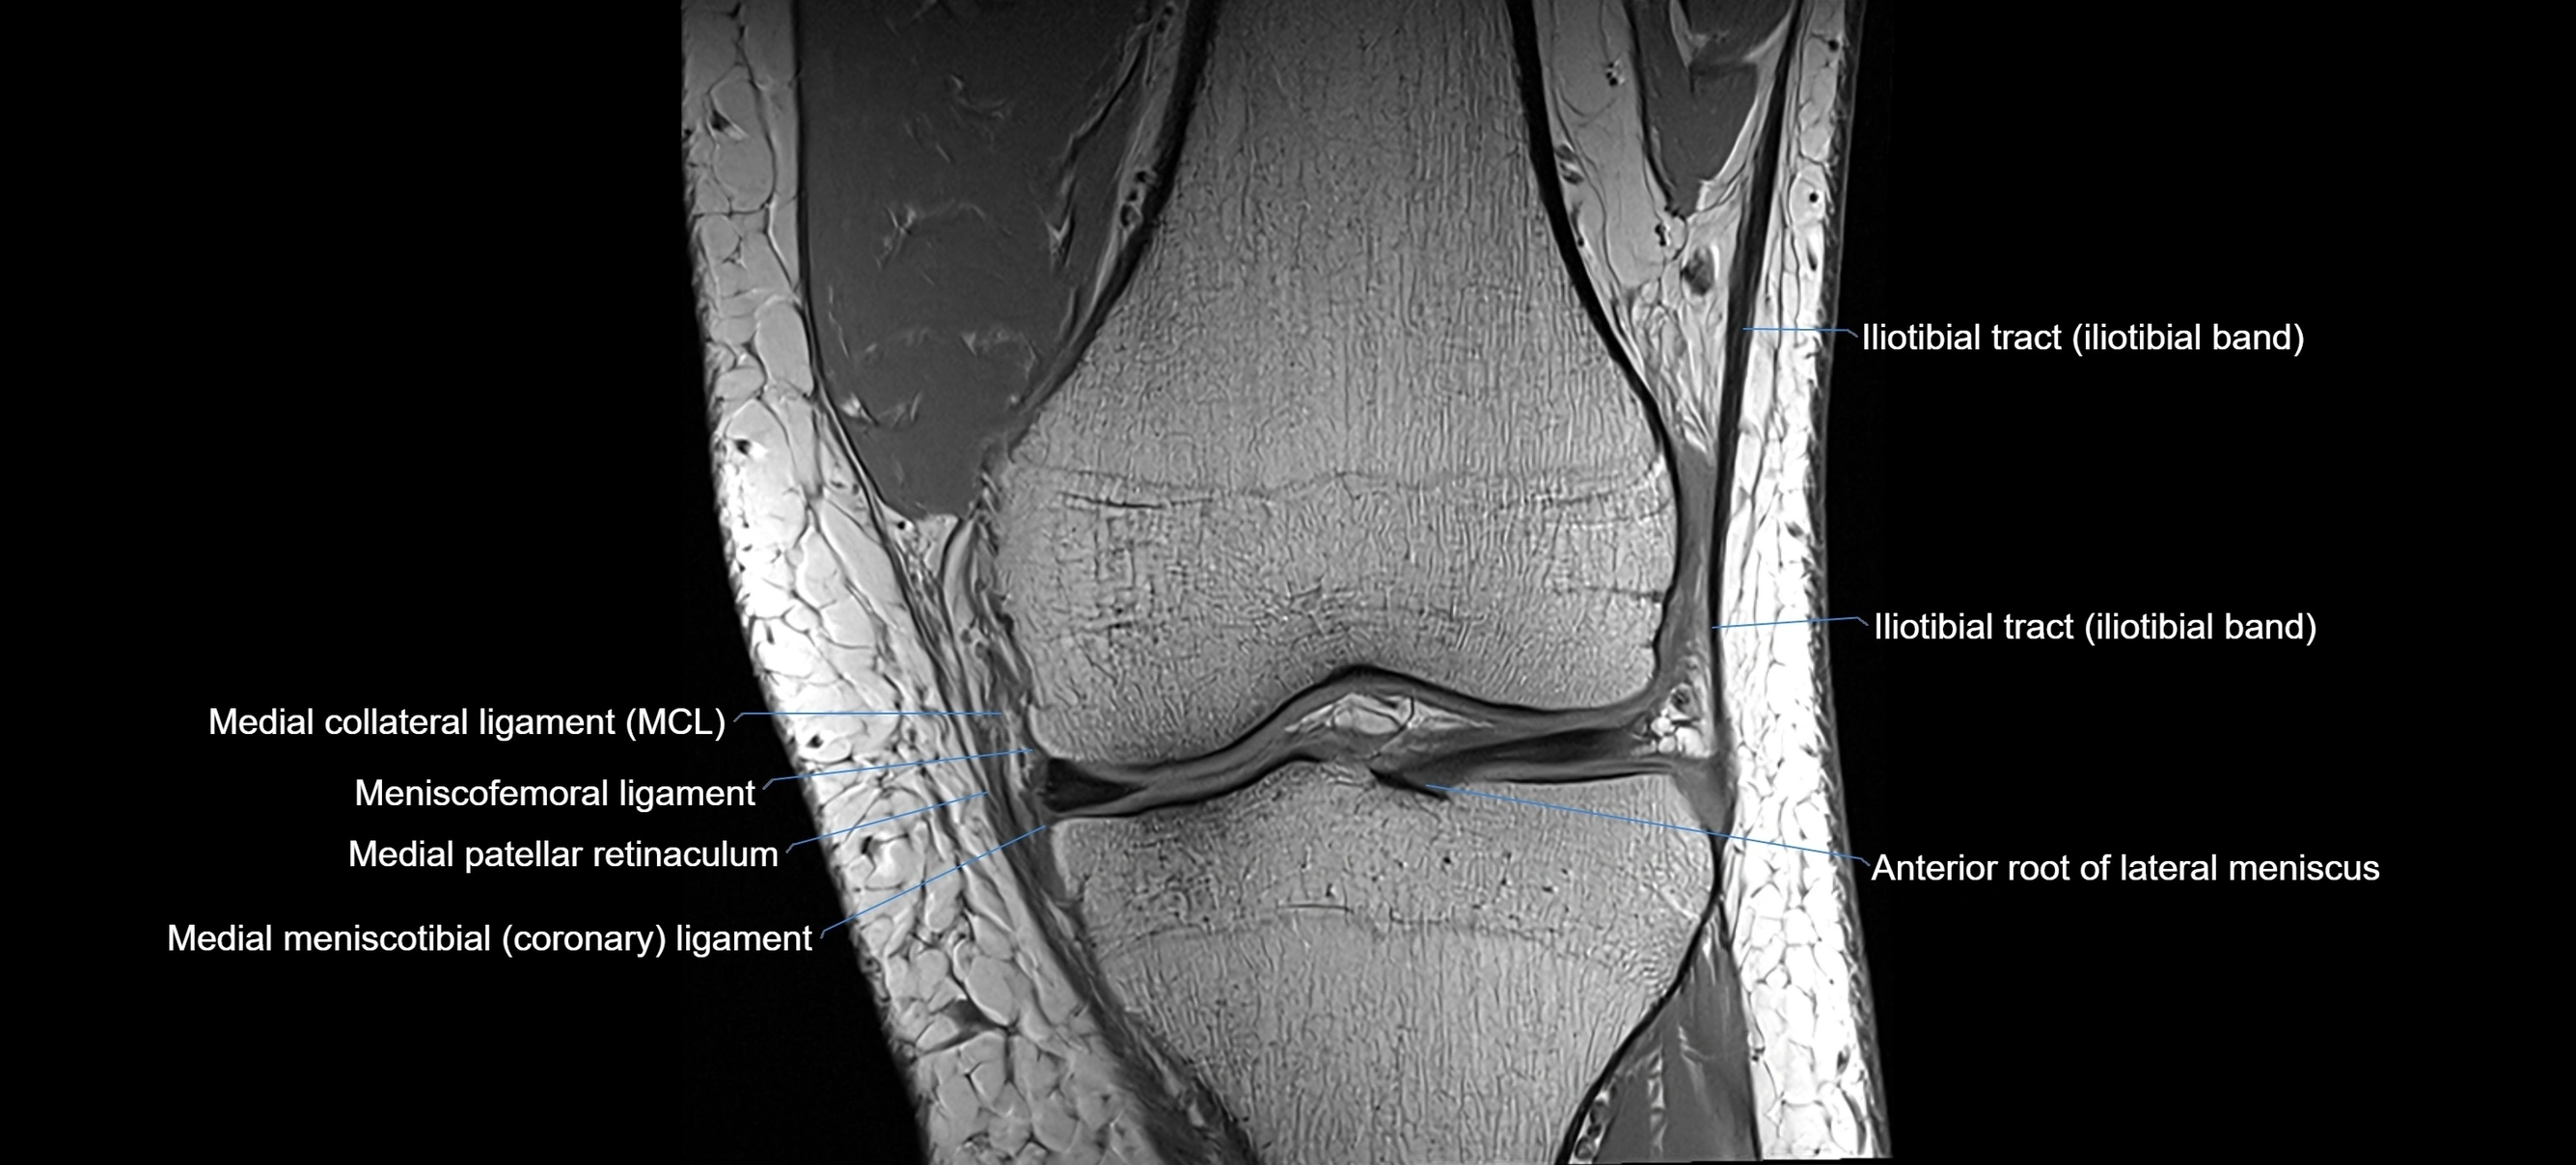

MRI images

image